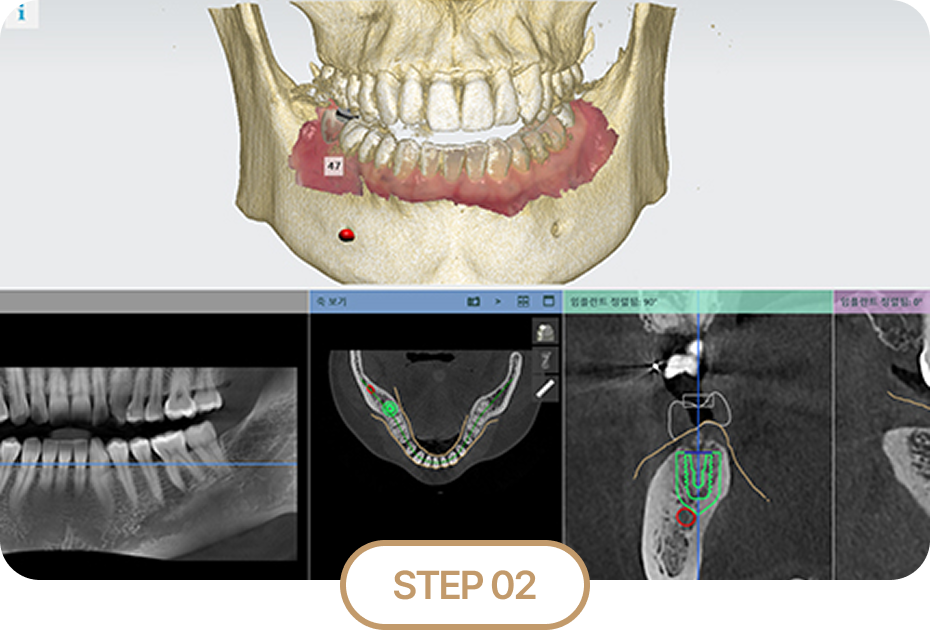

STEP 02

3D 모의 수술 후 치료 계획 수립

3D 디지털 모의수술